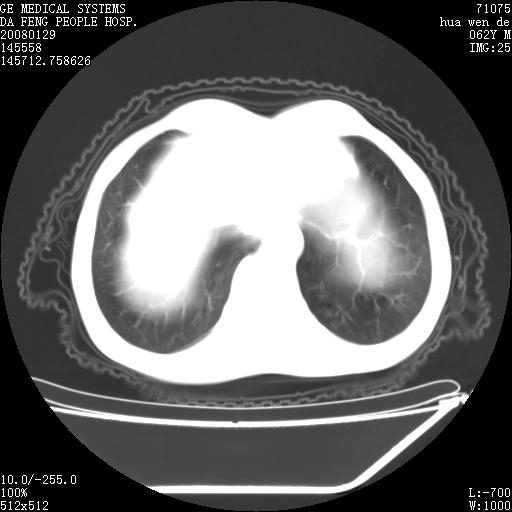

男性,67岁。作肺部检查时发现

胸腔胃多伴有左侧胸膜术后改变 ,本例不明显

胸腔胃不支持,

因无病史,暂考虑:贲门失驰缓症并肺部化脓感染(吸入性)

胸腔胃多伴有左侧胸膜术后改变~!!请提供病史!!

贲门失驰缓症.肺部感染伴脓肿形成。支持!是否吸入性要结合临床诊断,我们影像是看不出来的。但胸腔胃能排除(1.没有手术史支持,2.双侧胸廓对称,胸壁、肋骨及胸膜规整,3,食管壁明显扩张内壁光滑,胸腔胃黏膜皱襞多较厚)。

食管全程扩张,壁均匀不厚,喷门失弛缓症

右上肺空洞可见液平,临近肺野磨玻璃密度,考虑1.结核2.脓肿 支持!